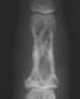

Dactylitis

Lytic phalangeal lesion